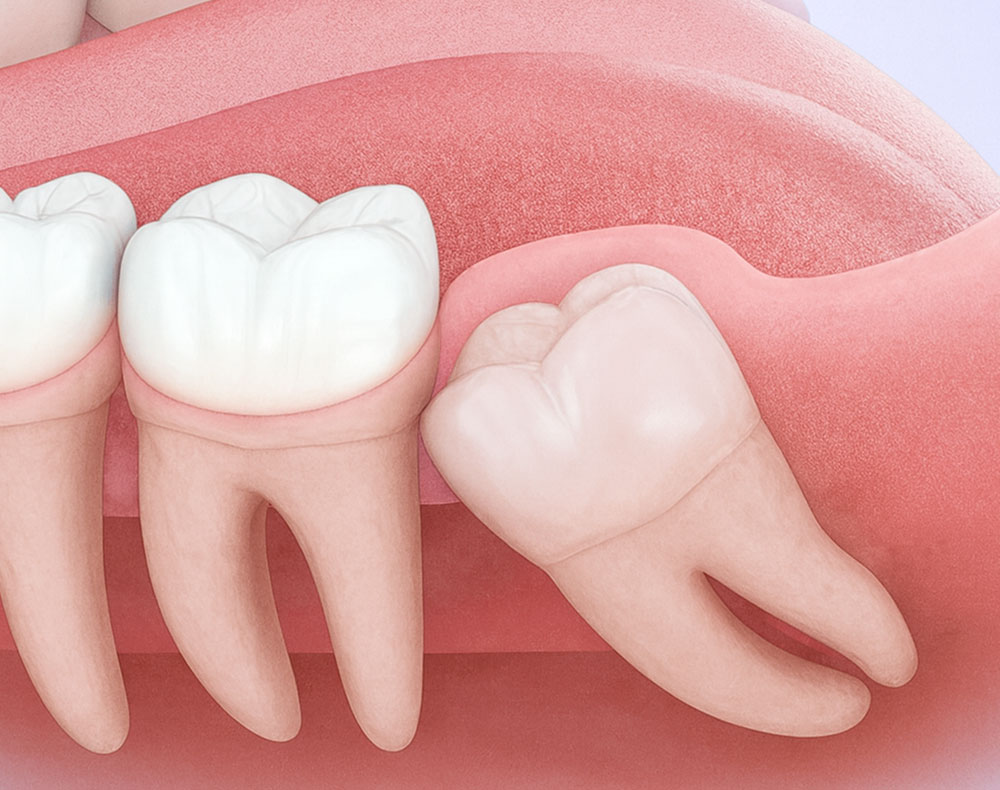

親知らずの抜歯

親知らず(智歯)は、20歳前後で一番奥に生えてくる歯です。まっすぐ生えて正常に噛み合わせに参加していれば問題ありませんが、多くの場合、スペース不足や傾斜して生えることで、痛みや腫れ、虫歯、歯ぐきの炎症を引き起こすことがあります。

• 斜めや横向きに生えていて、隣の歯を圧迫している場合

• 歯ぐきの奥に埋まっていて、炎症を繰り返す場合

• ブラッシングが届かず、虫歯や歯周病を引き起こしている場合